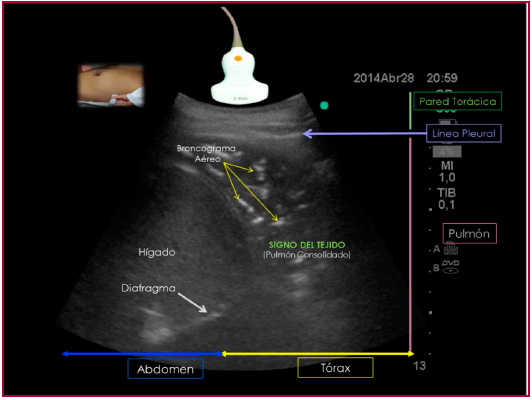

Patrón de consolidación

Se presenta cuando la aireación es menor del 10%, es decir, hay predominio del componente líquido y las imágenes que se visualizan son predominantemente reales (Figura 5). Se identifica ecográficamente por el “signo del tejido”, área de ecodensidad similar al hígado. Este patrón es común a entidades como neumonía, atelectasia, infarto pulmonar, tumores o contusión pulmonar. La orientación diagnóstica depende de diferentes características del “signo del tejido”, como la presencia de elementos internos, homogeneidad, bordes, vascularidad y modificaciones con maniobras respiratorias o posicionales. El cardiólogo debe reconocer la presencia de este patrón que le permite descartar causas de descompensación cardíaca como la neumonía.